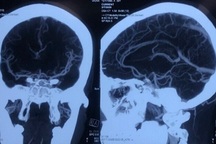

(Dân trí) - Đột quỵ xảy ra ở những người dưới 45 tuổi được gọi là đột quỵ ở người trẻ. Thói quen uống rượu bia, hút thuốc lá, ăn nhiều thực phẩm chiên rán, lười vận động… làm gia tăng đột quỵ ở người trẻ.

GS.TS Trần Bình Giang, Giám đốc Bệnh viện Hữu nghị Việt Đức (Hà Nội) cho biết mô hình bệnh tật của Việt Nam hiện có sự thay đổi từ các bệnh truyền nhiễm, bệnh nhiệt đới sang mô hình mới chủ yếu là các bệnh liên quan chuyển hóa như cao huyết áp, đái tháo đường, rối loạn lipid…. Một trong những hậu quả là bệnh lý mạch máu não, đột quỵ ngày càng tăng lên, ngày càng trẻ hóa.

"Tỷ lệ đột quỵ tăng lên ở người trẻ ngoài do dị dạng mạch máu bẩm sinh thì còn do thay đổi lối sống không rốt. Giới trẻ hiện nay uống rượu bia, hút thuốc lá, ăn nhiều thực phẩm chiên rán, sinh hoạt không lành mạnh… Lối sống đó khiến tỷ lệ xơ vữa mạch máu tăng rất nhanh, sớm, là nguyên nhân quan trọng tổn thương mạch máu não, GS Giang phân tích.

Theo GS Giang, với bệnh đột quỵ, việc đưa người bệnh sớm đóng vai trò rất quan trọng trong việc điều trị được hay không. 6 giờ đầu tiên từ khi khởi phát triệu chứng là thời gian vô cùng quý báu để chữa và phục hồi chức năng tốt nhất. Vì thế, cần đưa người bệnh đến các cơ sở y tế có khả năng xử lý được càng sớm càng tốt. Người dân cần nhận biết được những dấu hiệu đầu tiên cảnh báo đột quỵ, vận chuyển người bệnh an toàn và nhanh nhất đến cơ sở điều trị chuyên khoa.

Tại Việt Nam mỗi năm ghi nhận 200.000 người bị đột quỵ, gây tử vong đứng hàng thứ 3, gây tàn phế đứng hàng thứ nhất. Để phòng bệnh cần cách tránh các yếu tố nguy cơ bằng thói quen sống tích cực: không lạm dụng bia rượu, không hút thuốc lá hoặc sử dụng các chất kích thích, chế độ ăn uống điều độ, cân đối các chất, nên ăn nhiều rau xanh, hoa quả tươi, giảm muối, giảm mỡ, tập luyện thể dục hàng ngày, tránh tình trạng căng thẳng thần kinh quá mức và kéo dài.